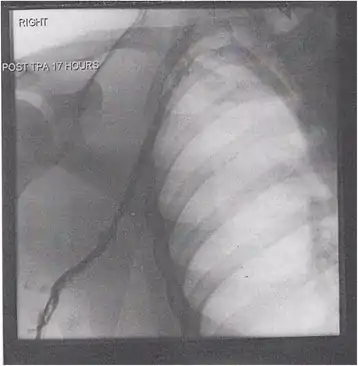

A venogram before catheter-directed thrombolysis against Paget–Schroetter syndrome, a rare and severe arm DVT shown here in a judo practitioner, with highly restricted blood flow shown in the vein

After treatment with catheter-directed thrombolysis, blood flow in the axillary and subclavian vein were significantly improved. Afterwards, a first rib resection provided thoracic outlet decompression to reduce the risk of recurrent DVT and the risk of sequelae from thoracic outlet compression.[133]